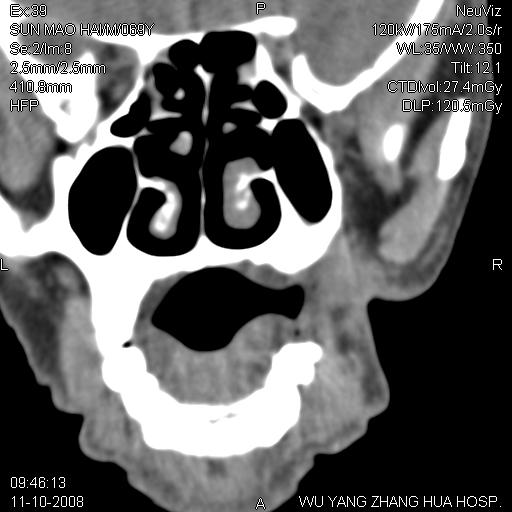

标题: CT16568:右面部瘘管半年余,无其它不适. [打印本页]

标题: CT16568:右面部瘘管半年余,无其它不适.

考虑右上颌异位齿(或斜向阻生齿)并根尖脓肿。

1.右上颌异位齿

2.右上颌化脓性骨髓炎

3.右下鼻甲肥大